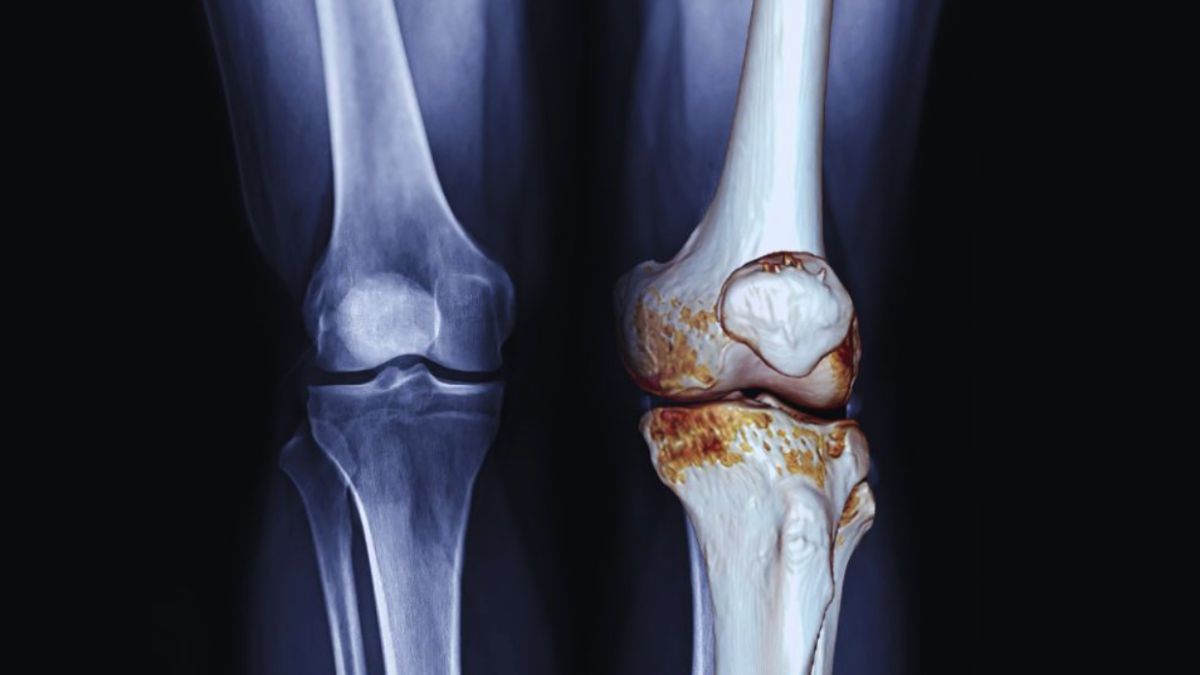

Miami joint pain treatment means finding ways to ease pain and improve how your joints move. This treatment can include many options that help people feel better step by step. Joint pain can come from various causes, like injury, arthritis, or wear and tear. Miami joint pain treatment aims to address the cause and help reduce the pain. There are many reasons why joints might hurt. Sometimes it is from an injury like a sprain. Other times it can be from health problems like arthritis. Aging can also cause joint pain because the tissues and cartilage get weaker. Overusing joints while playing sports or working can also cause pain.

Osteoarthritis

When the protective cartilage between bones deteriorates, osteoarthritis develops, resulting in pain and stiffness. Physical therapy as part of Miami joint pain treatment helps by strengthening surrounding muscles, improving flexibility, and reducing joint stress. Regular movement and guided exercises can ease discomfort and support better joint function for daily activities.